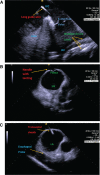

We offer the first reported case of a pulmonary vein isolation (PVI) procedure performed in a patient with two devices, specifically a cardiac resynchronization therapy defibrillator (CRT-D) and an Optimizer™ III device (Impulse Dynamics, Mount Laurel, NJ, USA), using the SANS FLUORO technique with zero fluoroscopy. In total, this patient had six leads traversing the right atrium, including two right atrial leads, three right ventricular leads-two associated with the Optimizer™ system and one implantable cardiac defibrillator lead-and a left ventricular lead.